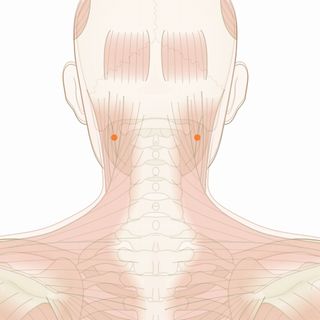

体の特徴を診ると、右頚部、右肩、背中のコリが強い。右目の症状とこれらのコリには深い関係があると判断した。 また、左足首の内側周辺に冷えが強いため、右上と左下でのバランスを調える必要性を感じた。右上と左下を意識した施術を行った。 1回目後、目の奥が気にならなくなったが、頚(後)と背中のコリが残った。 2回目後、症状はほぼ消失。施術を終了した。

使用したツボ